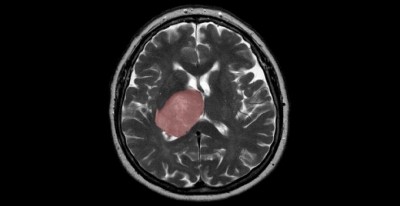

Toronto, January 6 (IANS): Researchers have found that the healing process that follows a brain injury -- from trauma to infection and stroke -- could spur tumour growth.

The finding, published in the journal Nature Cancer, could lead to a new therapy for glioblastoma patients who currently have limited treatment options with an average lifespan of 15 months after diagnosis, the researchers said.

"Glioblastoma can be thought of as a wound that never stops healing," Dirks said.

It suggests that some glioblastomas start to form when the normal tissue healing process, which generates new cells to replace those lost to injury, gets derailed by mutations -- possibly many years before patients become symptomatic, Dirks said.

Once a mutant cell becomes engaged in wound healing, it cannot stop multiplying because the normal controls are broken and this spurs tumour growth, according to the study.